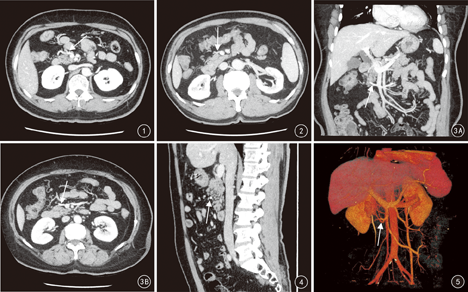

本组117例形成胃结肠静脉干,依据属支汇合情况不同分为3型,按所占百分比由高到低依次为胃胰结肠干型66.7%(78/117)、胃胰干型19.6%(23/117)、胃结肠干型13.7%(16/117),见表1。典型病例见图1,图2,图3,图4,图5。

胃结肠静脉干各属支血管显示效果评定:胃网膜右静脉117例、右结肠静脉92例、中结肠静脉26例,显示效果均达到3级;胰十二指肠上前静脉101例,显示效果1级33例,2级61例,3级7例。

胃网膜右静脉117例:向前上方91例,右前方9例,右前下方15例,后方及上方各1例。右结肠静脉92例:向右后下方64例,右前上方3例,右前方2例,右前下方3例,右后上及右后方各10例。中结肠静脉26例:向右前下方13例,向右前上方7例,前方4例,右后上以及右后下方各1例。胰十二指肠上前静脉101例:向后上方61例,后下方21例,后方19例。以上胃结肠静脉干各属支均未发现向左侧走行者。

胰十二指肠上前静脉汇入点变异较大,本组显示胰十二指肠上前静脉101例,其中汇入胃网膜右静脉者40例,汇入右结肠静脉者43例,汇入胃网膜右静脉与右结肠静脉合干者4例,直接汇入胃结肠静脉干者14例。本研究结果显示以汇入胃网膜右静脉与右结肠静脉者最多,分别占39.6%(40/101)和42.6%(43/101)。